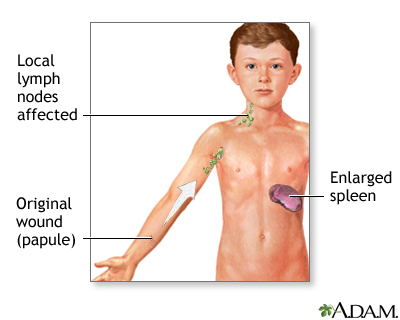

Cat Scratch Fever

Cat Scratch Fever Cat Scratch Fever: Causes, Symptoms

Cat Scratch Fever: Causes, Symptoms  High-risk Zone for Cat Scratch Disease

High-risk Zone for Cat Scratch Disease  Cat Scratch Disease | Healthy Pets

Cat-scratch disease | Radiology  Cat Scratch Disease and Your Child

Cat Scratch Disease and Your Child PDF) Cat-scratch disease: A wide